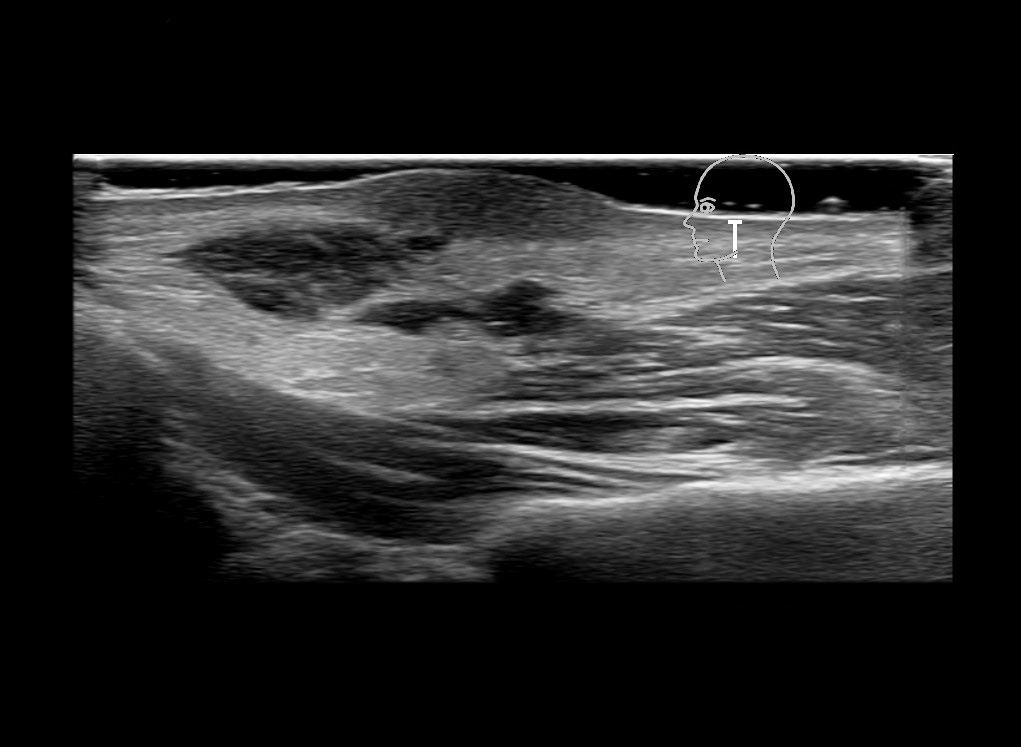

With ultrasound signs of inflammation can be visualized. Edema can be seen as a hyperechoic appearance of the subcutaneous fat, sometimes separated by hypoechoic fluid filled area’s, known as cobblestone appearance. Increased vascularization (hypervascularity) can be seen on colour Doppler. An abscess will appear as a fluid collection appearing as an irregular hypoechoic area with heterogeneous internal echoes and a thickened wall. Posterior acoustic enhancement can be present, and there is vascularity around but not within the mass. Under ultrasound guidance, abscesses can be managed by needle aspirations (18G) under antibiotic cover.

Study the first image to recognize the different layers. If you are sure about the layers, swipe to the second image to view the answer (if applicable).